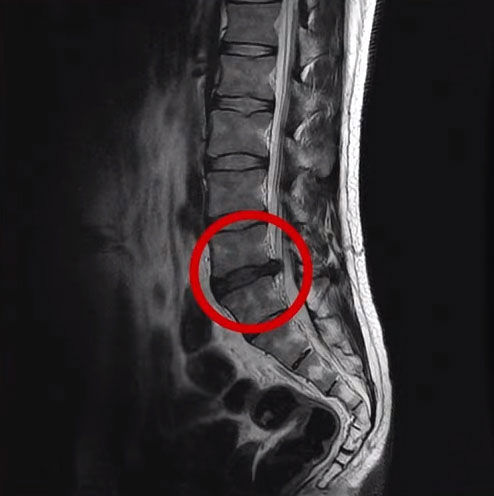

특히 만성요통 환자는 거의 대부분 퇴행성허리디스크를 갖고 있습니다. 그래서 허리가 장기간 아팠던 분들은 MRI를 한 번도 찍어보지 않으셨다면, 한 번 찍어보는 것이 큰 의미가 있습니다. 퇴행성허리디스크란 디스크가 퇴행되어 늙어버린 것을 말하는데, 그것도 여러 마디에 퇴행성허리디스크가 있는 사람들이 많습니다. 퇴행이란 허리가 늙고, 약해지고, 기능이 떨어졌다는 것입니다. 이렇게 퇴행성허리디스크가 있으면, 건강한 사람에게는 아무 것도 아닌 일상적인 일들이 무리가 될 수 있습니다. 특히 1시간 이상 오래 앉아있는 것, 1시간 이상 운전하는 것, 등산, 골프 등 허리에 무리가 되는 활동이나 운동이 통증을 더 심하게 만들 수 있습니다.